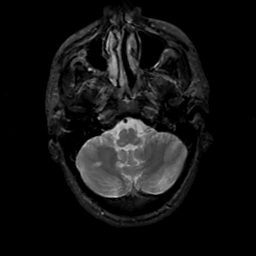

MR Study #14, June 2, 1991 -- Slice #9

[Home][Help][Clinical][Tour 1][Tour 2] Slice 9